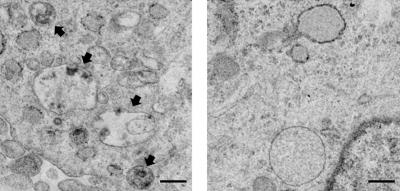

In AD, various biochemical functions of brain cells go awry, leading to progressive neuronal damage and eventual memory loss. One example is the cellular disposal system, called autophagy, which is disrupted in patients with AD, causing the accumulation of toxic protein plaques characteristic of the disease. Jae-sung Bae and colleagues had earlier noted that the brains of AD patients have elevated levels of an enzyme called acid sphingomyelinase (ASM), which breaks down cell membrane lipids prevalent in the myelin sheath that coats nerve endings. But whether increased ASM directly contributes to AD (and if so, how) was unclear.

The group now finds that these two defects are linked. In mice with AD-like disease, elevated ASM activity clogged up the autophagy machinery resulting in the accumulation of undigested cellular waste. Reducing levels of ASM restored autophagy, lessened brain pathology, and improved learning and memory in the mice. Provided these results hold true in humans, interfering with ASM activity might prove to be an effective way to slow—and possibly reverse—neurodegeneration in patients with AD.